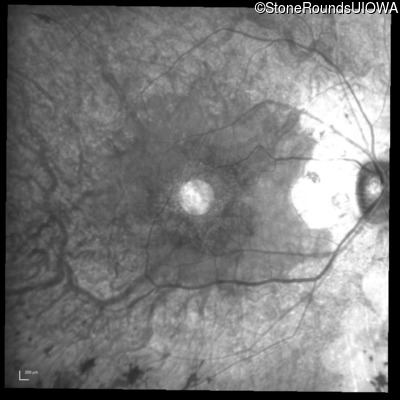

Infrared Fundus Photograph - Right - 20/25 -2 sc

Exemplar